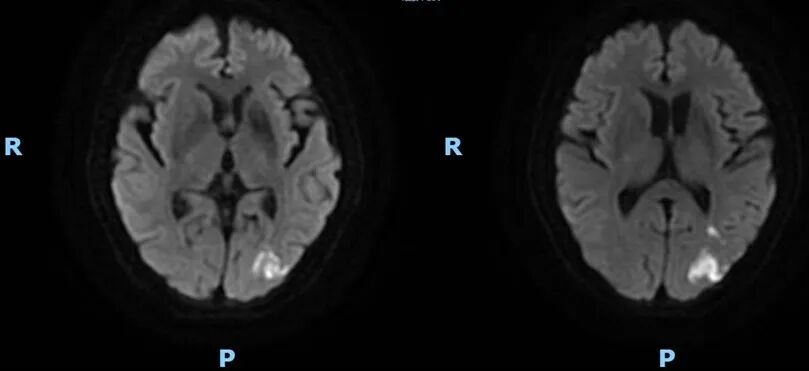

2022-02-05 颅脑MR。

导丝怎么扩【载药时代 球扩天下】NOVA DES®颅内药物洗脱支架在颈内动脉颅内段重度狭窄的应用二例!_https://www.jmylbn.com_新闻资讯_第23张

DWI

导丝怎么扩【载药时代 球扩天下】NOVA DES®颅内药物洗脱支架在颈内动脉颅内段重度狭窄的应用二例!_https://www.jmylbn.com_新闻资讯_第24张

MRA

重要影像结论:左侧额顶枕叶梗死灶。